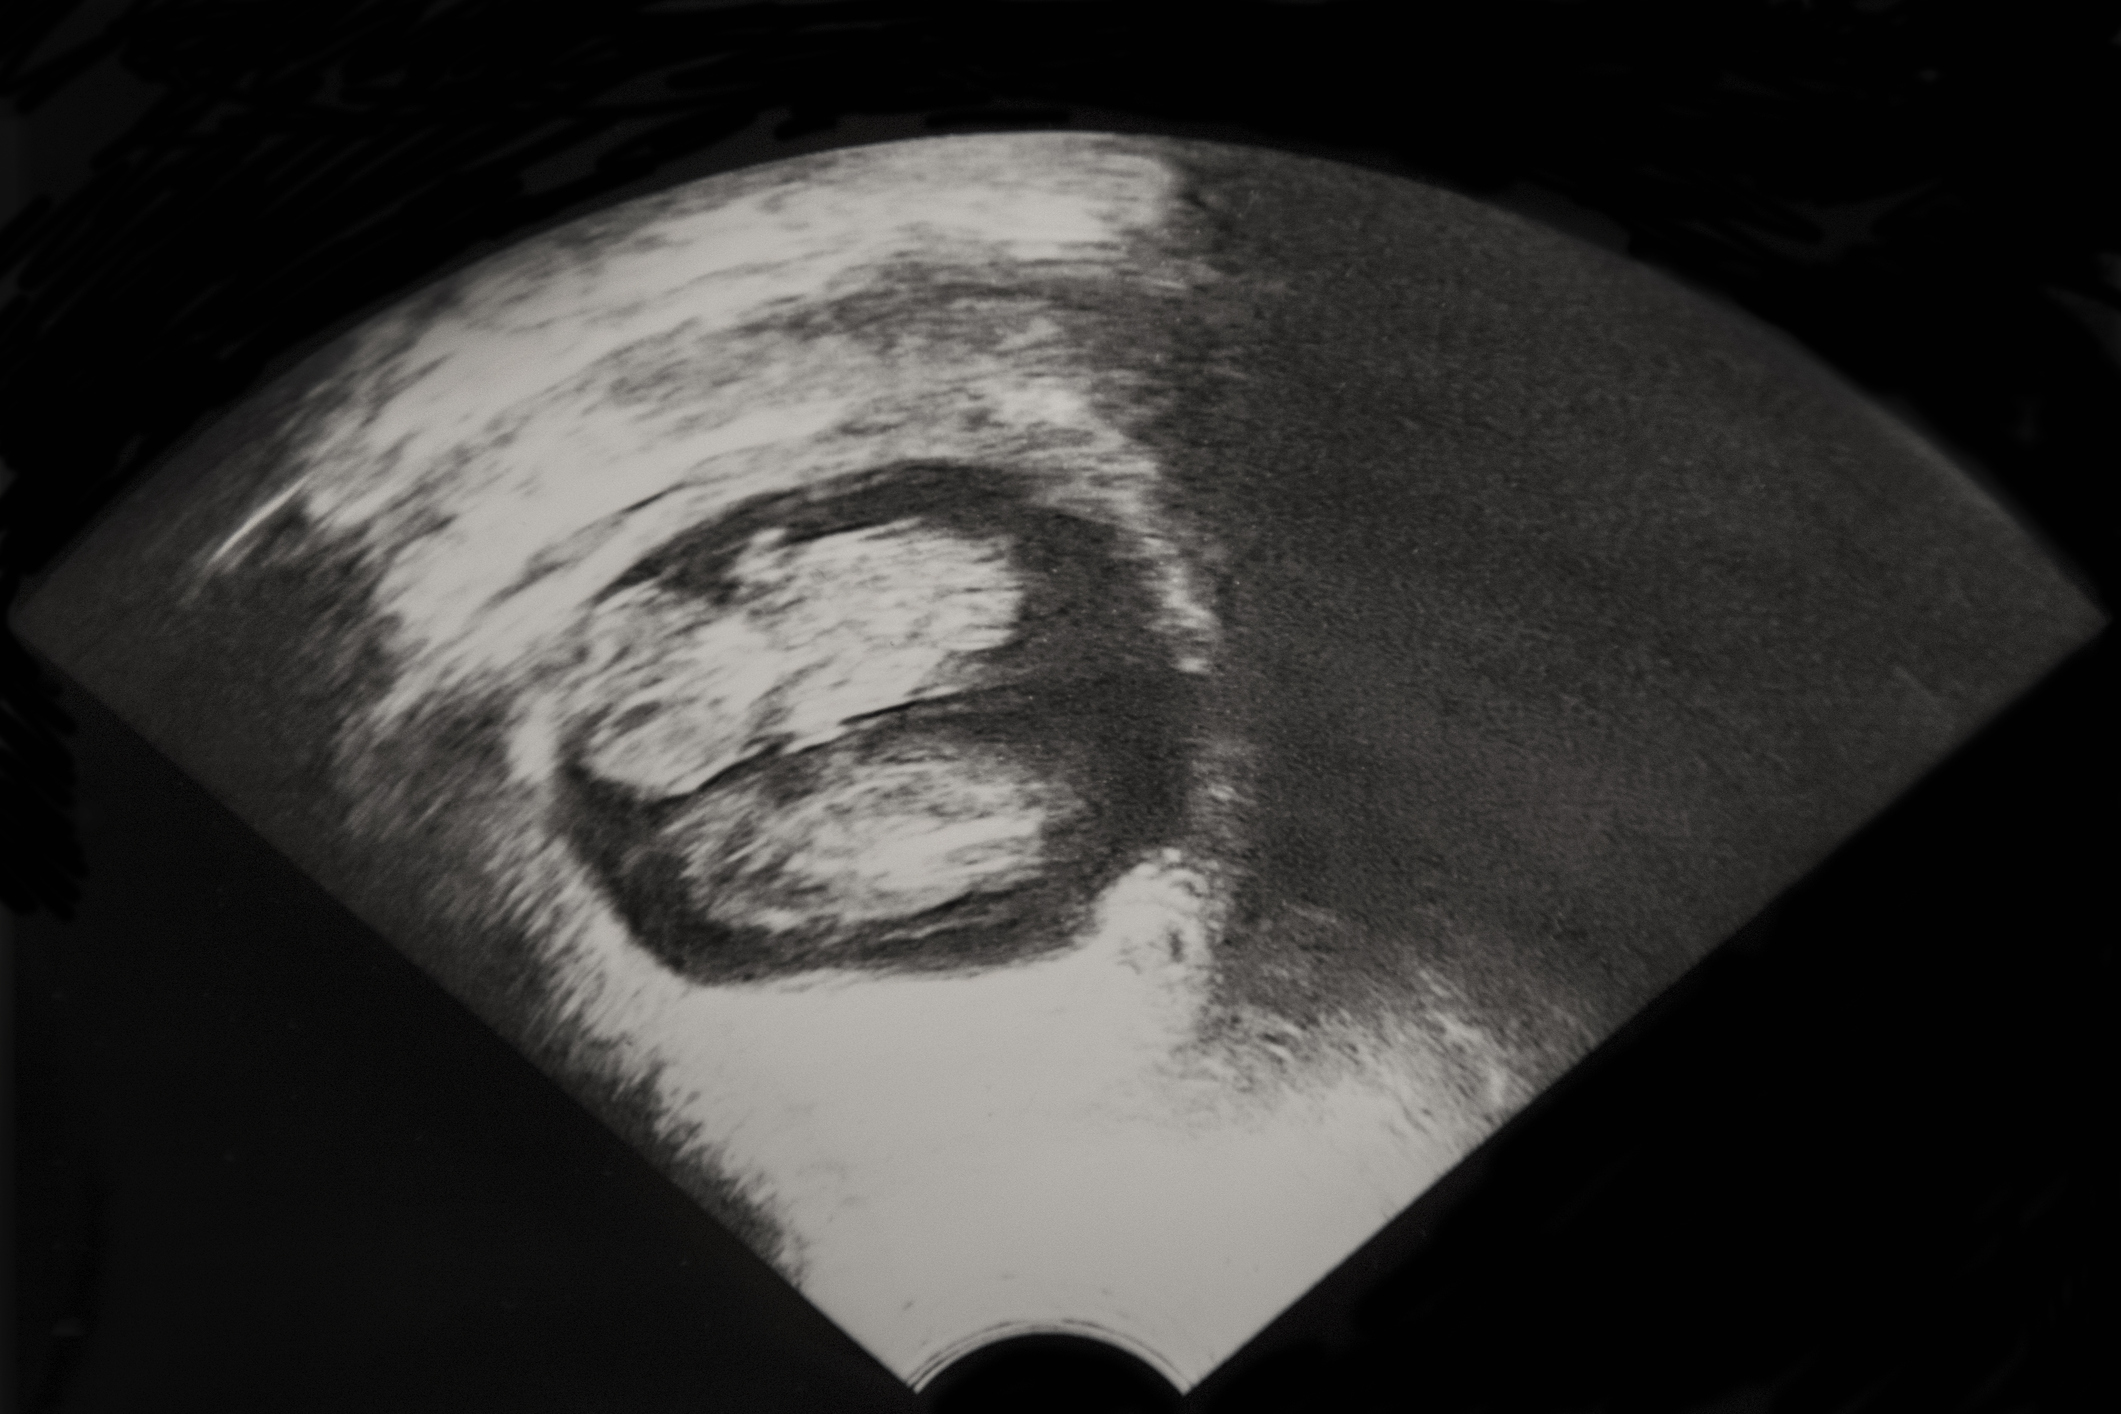

Fetal Twins Pregnancy Ultrasound Normal Vs Abnormal Image Appearances Multiple Gestations USG

Fetal Twins Pregnancy Ultrasound Normal Vs Abnormal Image Appearances Multiple Gestations USG How To Tell Identical Twins On Ultrasound But the best way to determine if twins are identical or fraternal is through examining their dna, since identical twins have the same dna. However, identical (monozygotic) twins might share an amniotic sac or have separate sacs depending on how early the egg. However, when a twin pregnancy is evaluated by ultrasound, it's impossible to tell directly whether the twins. How To Tell Identical Twins On Ultrasound.